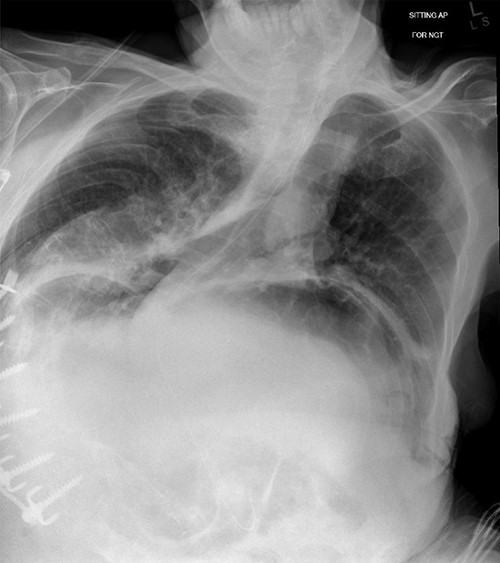

A 67-year-old man presented to the emergency department with sudden onset epigastric abdominal pain and vomiting, on a background of a known hiatus hernia awaiting surgical management. The patient continued passing flatus but was not able to tolerate any per oral fluid intake, vomiting any intake that was attempted. Medical history was relevant for severe KS, spina bifida, reflux, recurrent urinary tract infection, and an anterior approach spinal fusion surgery. Examination was significant for severe KS, with a soft and non-tender abdominal examination. Biochemically, the patient had a very mildly raised white cell count of 12.6 † 109/l. A CT of the abdomen and pelvis was obtained that identified the progression of a known hiatus hernia in comparison with an earlier CT, containing the distal portion of the stomach. The CT showed a distended and fluid filled oesophagus and stomach, along with fat stranding around the distal stomach, concerning for obstruction and possible strangulation of the moderate hiatus hernia, along with the known severe KS (see Figs 1 and 2). A nasogastric tube was placed to decompress the stomach (see Fig. 3). Following discussion with the patient regarding their current presentation and risks of operative management, laparoscopic hiatus hernia repair and fundoplication was undertaken, which was uncomplicated, although the dissection was difficult secondary to the severe scoliosis. Intra-operatively, it was noted that the hernial sac contained a grossly dilated stomach, with all hernial contents assessed as being viable, with nil signs of ischaemia. The peritoneal sac was not resected and left in situ, with a four-stitch horizontal posterior cruroplasty undertaken, along with a 180-degree anterior fundoplication. There was concern that recovery may be complicated by respiratory failure due to the severe KS; however, the patient had no respiratory compromise, begun passing flatus, opened his bowels, and tolerated a puree diet in the days following the operation. At post-operative clinic review 4 months following the hiatus hernia repair, the patient was well, described nil issues, and was tolerating a full diet.

Chest X-ray showing nasogastric decompression of hiatus hernia, along with severe kyphoscoliosis.